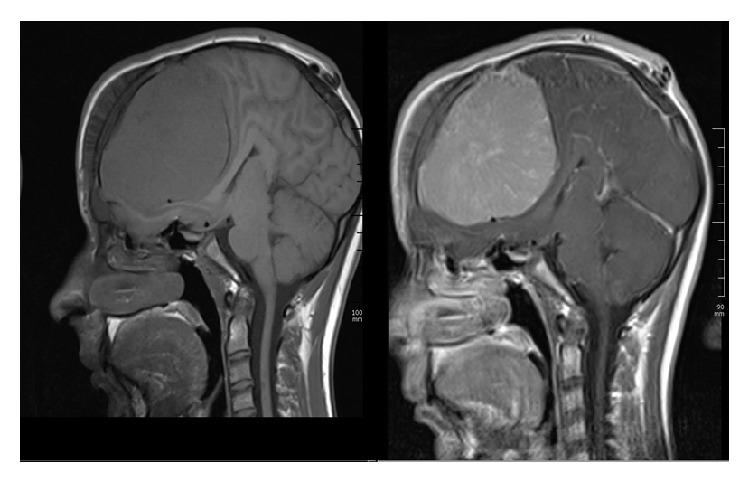

Objective. Meningiomas are benign primary meningeal tumors and are seen rare in children and adolescents. Clinical Presentation and Intervention. A 15-year-old Turkish boy reported a 1-month history of headache and blurred vision in both eyes. His visual acuity was 0.3 in both eyes with papilledema. Magnetic resonance imaging showed a 77 × 97 × 77 mm intracranial-extra-axial frontal lesion which compresses the chiasm. He was diagnosed with intracranial meningioma and referred to neurosurgery clinic. Conclusion. Ophthalmologists should be aware of the fact that papilledema and low vision can be caused by an intracranial tumor which compresses optic chiasm.

目的。脑膜瘤是原发性良性脑膜肿瘤,在儿童和青少年中罕见。临床表现与干预。一名15岁的土耳其男孩报告有1个月的头痛和双眼视力模糊病史。他双眼视力均为0.3,伴有视乳头水肿。磁共振成像显示一个77×97×77毫米的颅内-轴外额叶病变,压迫视交叉。他被诊断为颅内脑膜瘤,并被转诊至神经外科诊所。结论。眼科医生应意识到视乳头水肿和视力低下可能由压迫视交叉的颅内肿瘤引起。